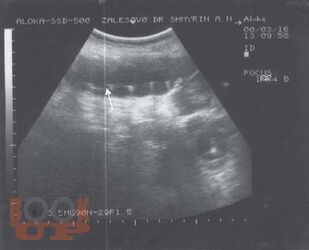

Ультразвуковая диагностика заболеваний толстой кишки

Шмырин А. Н. Ультразвуковая диагностика заболеваний толстой кишки : атлас / А. Н. Шмырин. - М. : Медпрактика-М, 2007. - 48 c. - ISBN 9785988030959. - Текст : электронный // ЭБС "Букап" : [сайт]. - URL : https://www.books-up.ru/ru/book/ultrazvukovaya-diagnostika-zabolevanij-tolstoj-kishki-3675620/ (дата обращения: 22.04.2026). - Режим доступа : по подписке.

Атлас представляет собой учебное пособие для начинающих специалистов и всегда доступный справочник для профессионалов. Форма компоновки материала позволяет быстро получить иллюстрацию патологического процесса и его описание.

Атлас рассчитан на специалистов по ультразвуковой диагностике, проктологов, гастроэнтерологов.